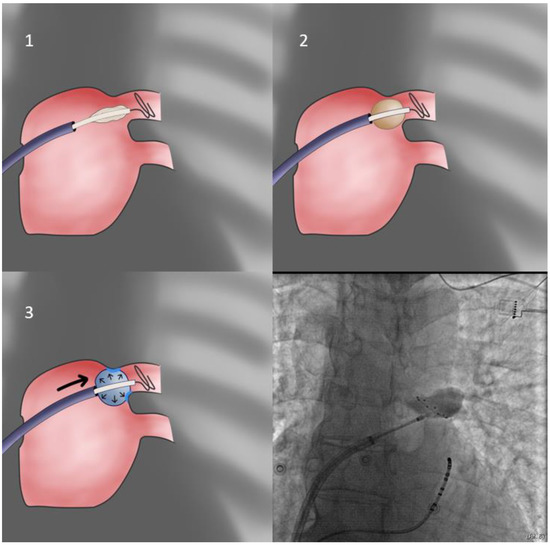

- In cases of extremely sized antra and despite proper orientation, sealing is unattainable; the operator may elect to push the sheath forward only after freezing has begun, since freezing increases CB diameter from 26 to 28 mm, rendering it more likely to properly occlude the antrum (delayed occlusion approach—Figure 4). Usually, the cue for sheath pushing is the initiation of a steep temperature drop on the monitoring console screen, several seconds after freezing has commenced. In even rarer cases, where this approach is ineffective, and conversion to a point-by-point approach is undesirable, one may deliver lesions in a sequential manner, targeting each quadrant of the antrum separately, without occlusion, evaluating the effect after completion of the quartet of applications (segmental approach).